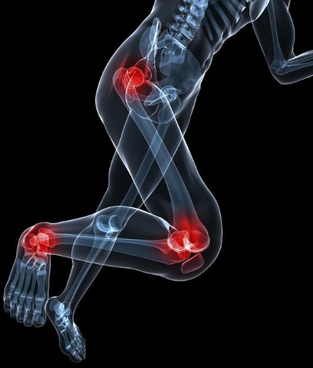

Why Symptoms of Foot Knee and Hip Pain can be Misleading Hip to Toe Podiatry Physiotherapy on The Gold Coast

Hidden Culprits How the Foot Ankle Hip and Pelvis Can Contribute to Knee Pain LONGEVITY PERFORMANCE INSTITUTE

Heel and Knee Pain Causes Physical Therapy Spokane Valley